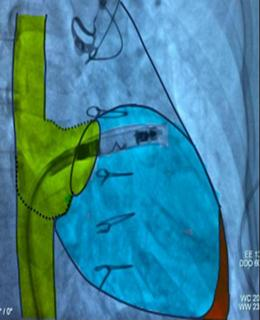

Under fluoroscopic guidance, the delivery catheter was advanced through the right atrium. Significant resistance was encountered as the catheter tip repeatedly abutted the ventricular wall due to the limited chamber size. To overcome this, the catheter was reshaped into a “hockey-stick” configuration developed by our team (Fig. 4–9). This modification enabled safe passage through the tricuspid valve and facilitated navigation to the apical-septal region. Contact mapping confirmed optimal electrical parameters before fixation, and the device was screwed into the septum. Device interrogation demonstrated proper function: pacing threshold 0.75 V at 0.4 ms, R- wave amplitude 6.0 mV, impedance 750 Ω, mode VVI, with estimated battery longevity of ~12 years.

Figure 4. Modified 'hockey-stick' curvature of the delivery catheter guiding the pacemaker toward the right ventricle

Figure 5. Implantation phase of the pacemaker

Figure 6. Fluoroscopic image showing the Aveir™ VR leadless pacemaker positioned in the right ventricular septum

Figure 7. Final position of the leadless pacemaker inside the small right ventricle

At the junction of the superior vena cava and right atrium, maximal deflection of the distal catheter segment was applied, followed by slight retraction, creating an acute 70–90° bend resembling a “hockey stick.” This configuration shortened the working length, allowing maneuverability in the restricted RV cavity. Crossing the tricuspid valve was guided by RAO 30° and LAO 40° projections to ensure septal alignment. In the apical-septal region, contact mapping (with the helix unreleased) confirmed acceptable parameters (R-wave ≥5 mV, threshold ≤1.0 V at 0.4 ms, impedance 400– 1500 Ω). Upon satisfactory values, the device was screwed into the septum with 1.5 turns. Perpendicular positioning was confirmed in orthogonal views, followed by a tug test. Repositioning was feasible if parameters were suboptimal.